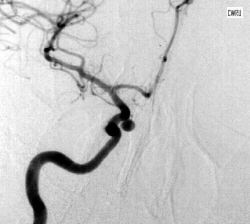

Refer to this picture for question 2.

2. Blood films related to the above appearance include: